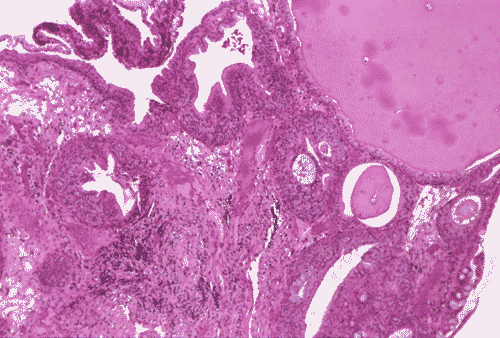

The biopsy material showed polypoid fragments with cystically dilated glands lined by columnar to cuboidal cells (Panel A, B, and C). Some of the glands were lined by transitional epithelium (Panel D), some were lined by a mixed transitional epithelium and mucin producing columnar epithelium (Panel E), and some were lined entirely by mucin producing columnar epitheliuim (Panel F) that closely resembled colonic epithelium. A mild to moderate degree of chronic inflammatory cell infiltration was also present. A mixed population of mucin producing columnar epithelium with transitional epithelium was also noted in many of the non-glandular surface epithelium (Panel G). No dysplasia was found.

DIAGNOSIS: Polypoid cystitis cystica et glandularis, intestinal type.